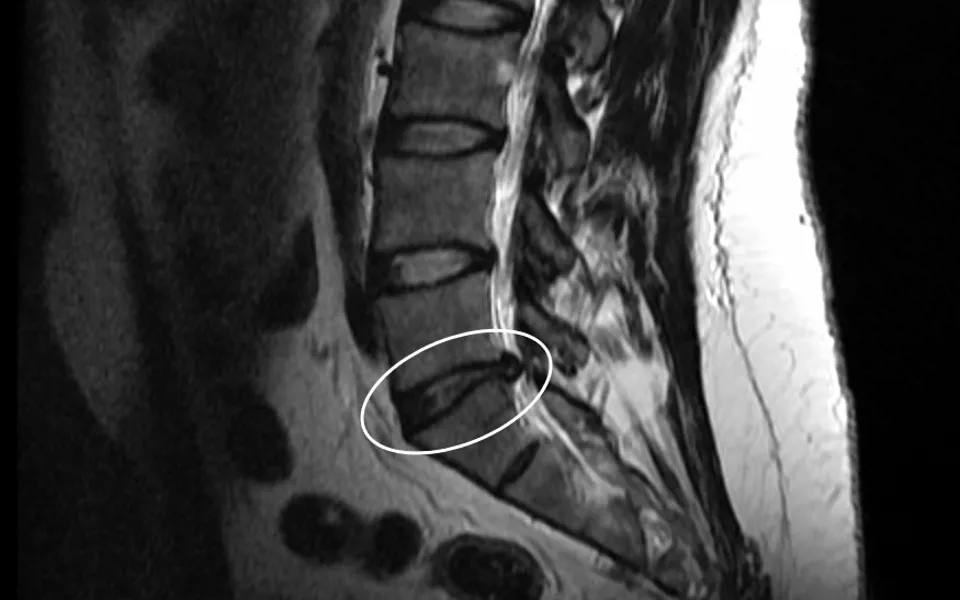

Una hernia se define como un desplazamiento localizado del material discal más allá de los límites del espacio discal intervertebral. Para que se considere localizado, el material discal desplazado debe ocupar menos del 50% de la circunferencia del disco (figura 3).

- Extrusión (figura 5), cuando, en al menos uno de los planos, cualquier distancia entre los bordes del material discal que se encuentra más allá del espacio discal es mayor que la distancia entre los bordes de la base, o cuando no existe continuidad entre el material discal desplazado y aquel que se encuentra dentro del espacio discal

Figura 5. Representación de una extrusión (en color verde claro) en un plano axial. Se puede apreciar como la base (raya en color azul oscuro) es menor que la distancia entre los bordes del material discal desplazado (raya en color verde oscuro).

Por otro lado, destacaron que si el paciente presenta una hernia extruida (ver figura 5), en un 83% de los casos llega a desaparecer.